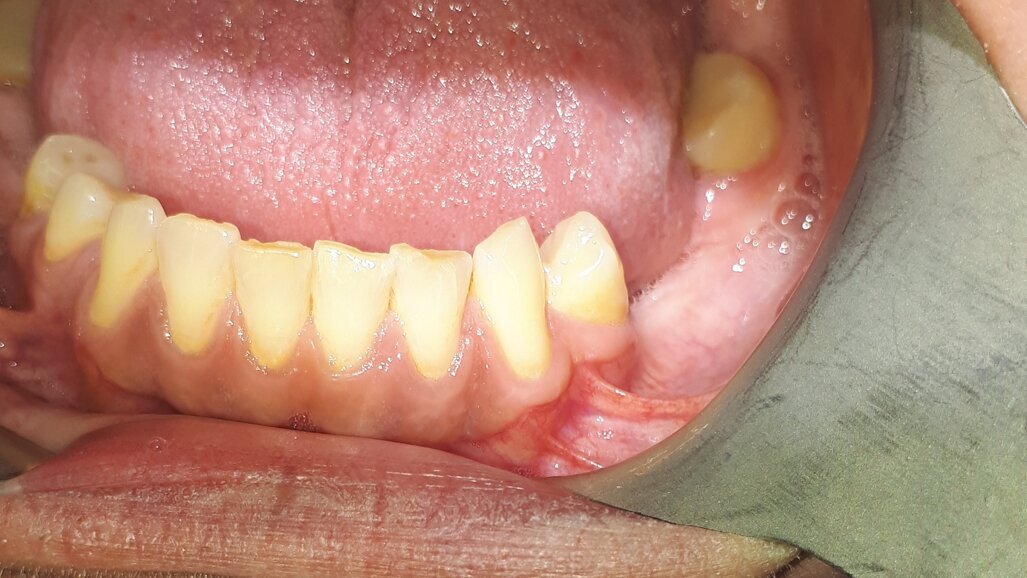

W badaniu wewnątrzustnym stwierdzono niewłaściwą higienę jamy ustnej i obfite złogi nazębne, próchnicową destrukcję koron zębów 27, 28, 47, głęboki ubytek próchnicowy zęba 48 z obnażeniem miazgi, złamanie korony zęba 22, braki międzyzębowe w szczęce i żuchwie oraz niewielkie, dyskretne wygórowanie tkanek miękkich pomiędzy zębami 32 i 33 niebolesne palpacyjnie.

Pacjent zgłosił się na wizytę kontrolną w maju br., tj. 1,5 roku po zabiegu. Badanie kliniczne nie wykazało nieprawidłowości, widoczne była jedynie dyskretna blizna pozabiegowa (Ryc. 3). Wykonane badanie CBCT ujawniło prawidłową strukturę i ubeleczkowanie wygojonej loży po torbieli (Ryc. 4).

Ryc. 3: Stan 18 miesięcy po zabiegu.